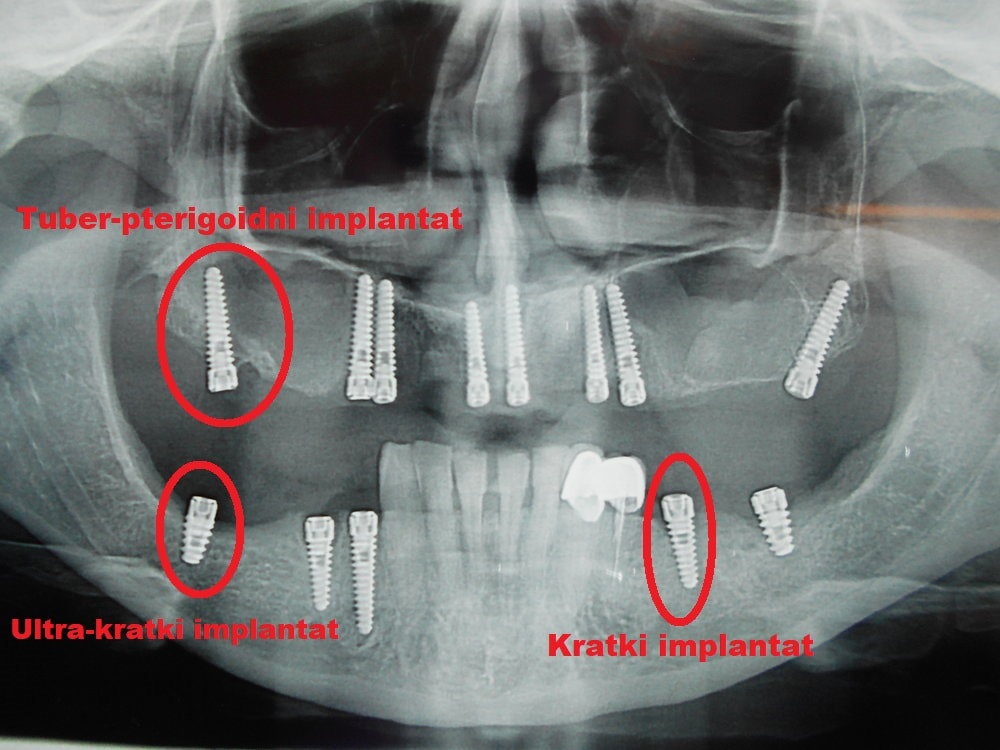

Tuber-pterigoidni implantat bez sinus lift procedure

Dentalna implantologija obuhvata hirurške procedure koje imaju za cilj funkcionalnu rehabilitaciju pacijenata upotrebom dentalnih implantata, odnosno metalnih elemenata koji se hirurški ugrađuju u gornju i donju vilicu.

Implantati mogu da imaju različiti oblik, mogu da se ugrade u različitim pozicijama i različitim tehnikama. Trenutno se većina implantata izrađuje od titanijuma.